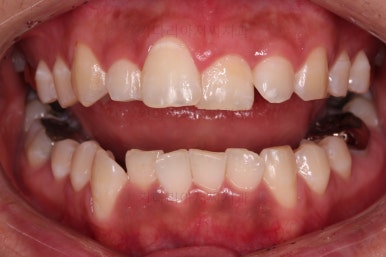

초진 시, 입 안의 모습이에요.

위아랫니가 삐뚤고 교합이 약간 맞지 않네요.

입 안만 보면 심플하게 교정하면 되겠다 싶지만, 문제는 다른 곳에 있었어요.

장치 부착 이후의 느낌도 봐주시고요.

치열이 점점 가지런해지죠?

조금만 더 하면 마무리를 할 수 있겠네요.